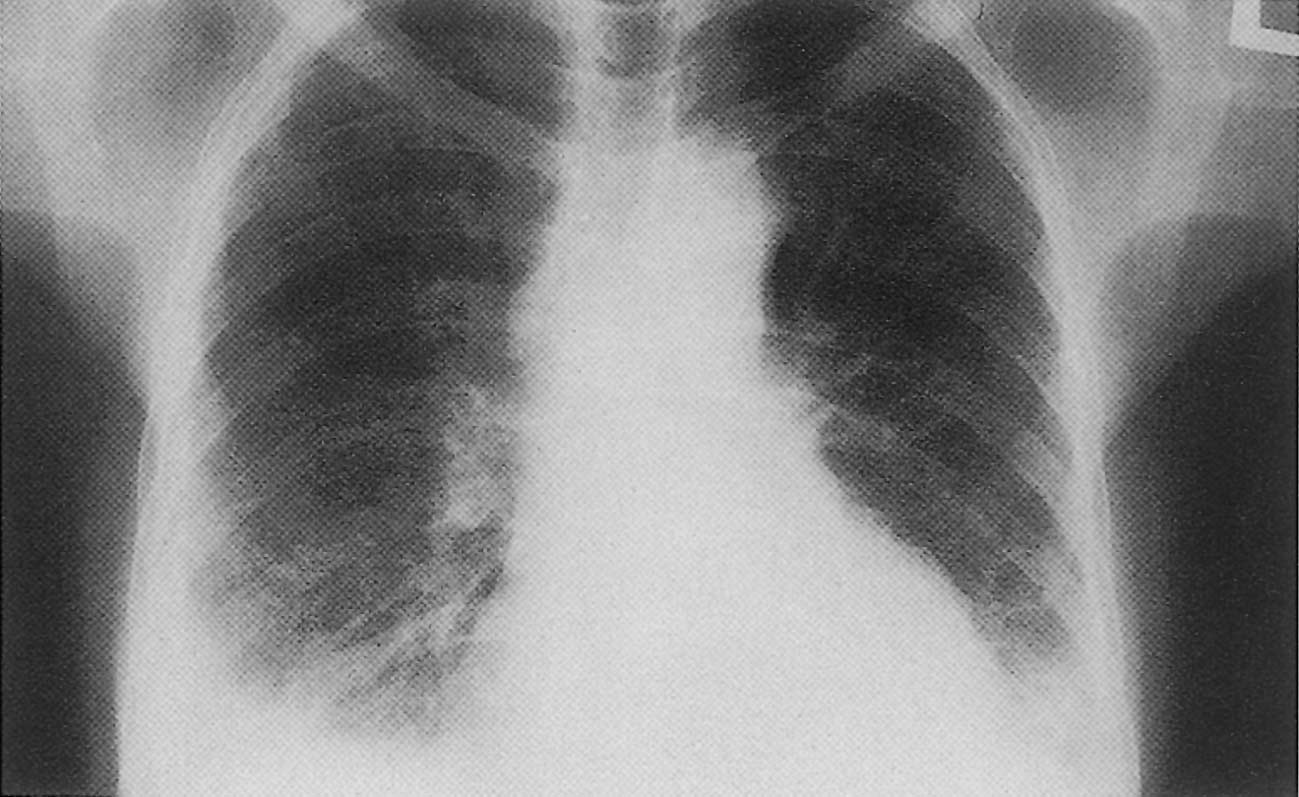

السائل النضحي: ويتصف بزيادة البروتين فوق 30غ/ل وتكون نسبة بروتين السائل إلى بروتين الدم أكثر من 50% ونسبة خميرة L.D.H في السائل إلى نسبتها في الدم أكثر من 60% أو أكثر من ثلثي الحدود العليا لمعيارها في المصل. وأكثر الأسباب إحداثاً هي: ذوات الرئة الجرثومية والفطرية والفيروسية والطفيلية والتدرن وخراجات الرئة والآفات الورمية والتنشئية البدئية في الجنب (ميزوتليوما) والانتقالية. ويكون السائل غالباً مدمى. وكذلك الآفات الدموية كابيضاضات الدم واللمفوما، والآفات الجهازية كالذأب الحمامي والداء الرثياني (صورة رقم1) والتهاب ما حول الشريان العقدي، وآفات البطن كخراجات تحت الحجاب (خراجة الكبد، التهاب المعثكلة (البنكرياس))، ومتلازمة ميغز Meig’s syndrom المترافقة بأورام المبيض وارتفاع البولة الدموية وداء الأمينت (الأسبستوز) والغرناوية (الساركوئيدوز) والارتكاسات الدوائية التحسسية واحتشاء الرئة.

انصباب جنب أيسر

ظهر في سياق مرض شبه نزلي لدى امرأة شابة